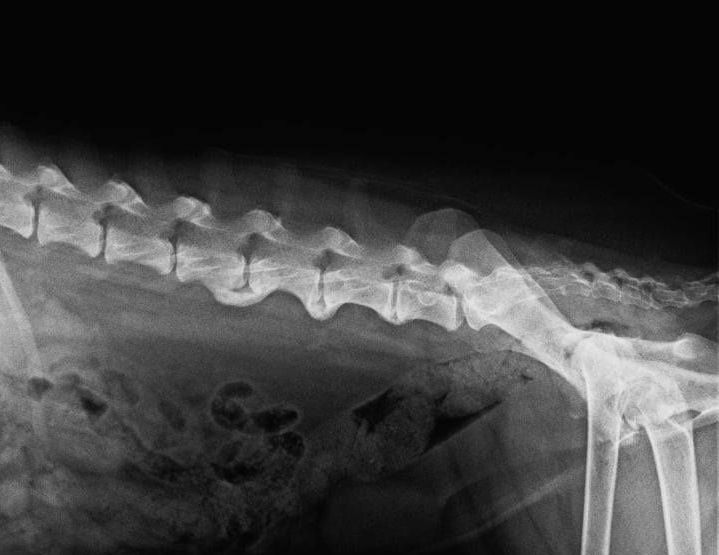

Ein Bandscheibenvorfall beim Hund tritt auf, wenn der gelartige Kern einer Bandscheibe aus dem Faserring austritt, das Rückenmark komprimiert oder sogar verletzt und/ oder auf umgebenden Nerven drückt.

- aufgezogener Rücken: der Rücken des Hundes zeigt in diesem Fall eine deutliche Kyphose (Katzenbuckel)

- Alter: ältere Hunde sind anfälliger für Bandscheibenvorfälle aufgrund von degenerativen Veränderungen in der Wirbelsäule.